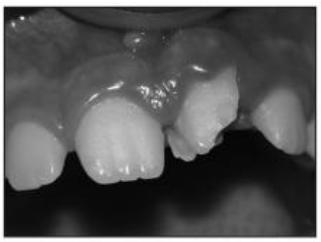

Considere a imagem, a seguir:

enunciado 1353520-1

A imagem, acima, representa: